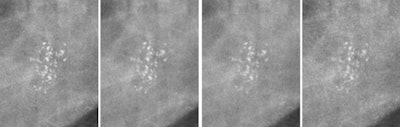

Example of an inserted calcification cluster converted to appear for the four detector types of the study at the same dose. From left to right: a-Se, CsI, CR NIP, CR PIP. All images courtesy of Dr. Alistair Mackenzie.How CR stacks up